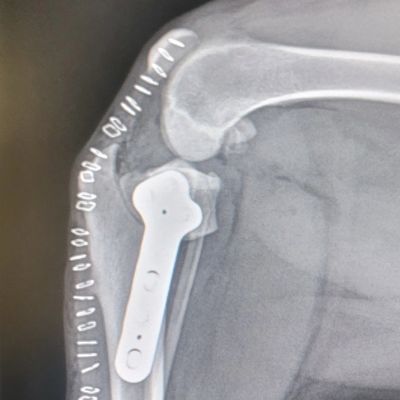

TPLO surgery - Cranial Cruciate Ligament Tear

- Affordable Orthopedic Surgery (TPLO, Fracture, Etc) Consultation.